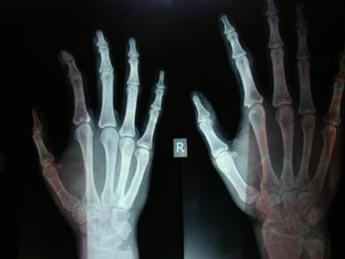

(图:王女士在医院拍的CT影像图)

杜爱华主任看到王女士全身严重浮肿,面部严重潮红,四肢关节严重变形歪斜,并且右手肘关节骨质变形增生成竹笋状骨刺。杜爱华主任通过从王女士的病情看来初步确诊为类风湿性关节炎。由于王女士全身大小关节都受到了或多或少的影响,杜爱华主任立即给王女士做了全面检查,清晰有力的判断出王女士确实是类风湿性关节炎。最后为王女士制定了相应的治疗计划。

接受两个疗程的治疗后,病情得到控制,有较明显好转。又经过1个疗程的治疗后,患者生活可完全自理,手指由变形歪斜不能自理到伸缩自如,全身浮肿完全消失,面部由严重潮红到白里透红,右手肘关节处严重变形增生的2寸长骨刺完全自然消失。复诊检查出各项指标达到临床标准。